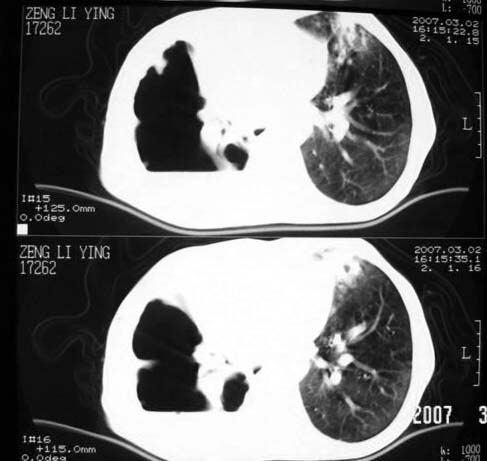

以下是引用dyqct在2007-3-2 22:04:00的发言:[br]考虑:1、右侧毁损肺伴支气管胸膜瘘(多条支气管与胸腔相通、液气胸);[br] 2、左肺浸润型肺结核。[br][br][br][br]